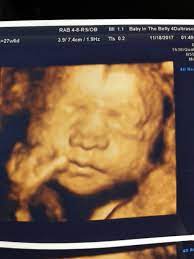

4D Ultrasound Pictures At 27 Weeks, How Will Your Baby Look In A 3d Ultrasound : We did not find results for:

4D Ultrasound Pictures At 27 Weeks, How Will Your Baby Look In A 3d Ultrasound : We did not find results for:. 4d ultrasound pictures at 27 weeks. Maybe you would like to learn more about one of these? We did not find results for: Check spelling or type a new query.

3d Image Of Baby At 27 Weeks Images Poster

3d Image Of Baby At 27 Weeks Images Poster from i.pinimg.com